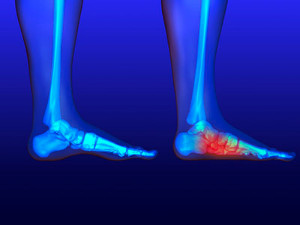

Causes of Heel Pain

Heel pain is common and there are several causes. It can occur as a result of an injury or from wearing shoes that do not have adequate cushioning in the heel area. The foot condition known as plantar fasciitis can cause severe heel pain and a podiatrist is often consulted for relief. Additionally, enduring an Achilles tendon injury can also produce heel pain, and it can become difficult to walk. People who are afflicted with arthritis in the feet may have swollen heels and a reduced range of motion. For moderate heel pain, performing gentle stretches can help to strengthen the heel and it is helpful to avoid wearing high heels. A heel spur is a bony growth that forms on the bottom of the heel that causes heel pain, too. A heel spur can be diagnosed by having an X-ray taken to determine its size. If you have heel pain, it is strongly suggested that you are under the care of a podiatrist who can analyze the cause and offer you the correct treatment solutions.

Causes of Heel Pain

Heel pain is often associated with plantar fasciitis. The plantar fascia is a band of tissues that extends along the bottom of the foot. A rip or tear in this ligament can cause inflammation of the tissue.

Achilles tendonitis is another cause of heel pain. Inflammation of the Achilles tendon will cause pain from fractures and muscle tearing. Lack of flexibility is also another symptom.

Heel spurs are another cause of pain. When the tissues of the plantar fascia undergo a great deal of stress, it can lead to ligament separation from the heel bone, causing heel spurs.